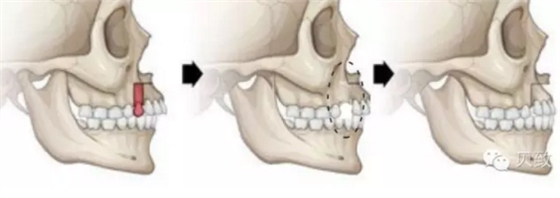

矯正時(shí)牙齒之所以能在口腔中移動(dòng),主要是因?yàn)榘栏难啦酃蔷哂薪K生改建的能力。牙槽骨的重建作用,有點(diǎn)類似于“拆東墻補(bǔ)西墻”。

當(dāng)牙齒向前移動(dòng),持續(xù)的壓力作用到牙槽骨上時(shí),受力部分的牙槽骨會(huì)逐漸被吸收,給牙齒的移動(dòng)開辟了空間。而包繞在牙齒后側(cè)的韌帶會(huì)受到牽拉,提示它需要修復(fù)因牙齒移動(dòng)所產(chǎn)生的縫隙啦,機(jī)體立即會(huì)長(zhǎng)出新的牙槽骨來填補(bǔ)多出來的空隙!這么一吸一補(bǔ),牙齒就能在牙槽骨中穩(wěn)穩(wěn)地移動(dòng)啦~

在改建周期完成以后,這顆牙齒依然被牙槽骨緊密包圍,不留空隙,但位置已經(jīng)產(chǎn)生變化了,完美解決牙列缺損、擁擠問題,何來牙齒傾斜松動(dòng)一說?